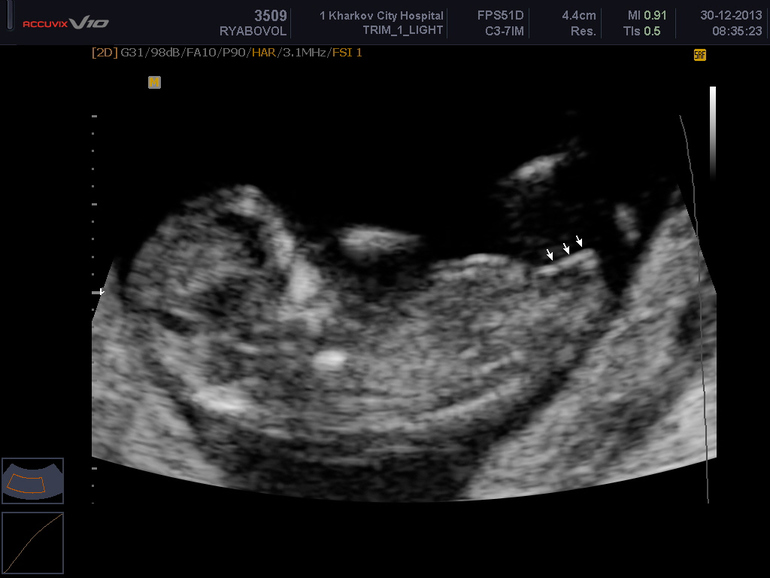

Сходили сегодня на плановое узи, анализы были плохими в-хгч и папп больше 3, но разрыв между ними 0,2 и вероятность генетических отклонений минимально все в норме. По всем гороскопам, совместимостям, гадалкам, знакам у нас мальчик, девочка не проскакивала ни разу. Мы делал. Тест на пол и сказали мальчик) спрашиваем узиста ну что сына? А он смеется и говорит доча думаю) мы в шоке! Он показал почему доча, сейчас прикреплю фото) я не против дочи, да и муж тоже, но все же ждали сыну) он очень уверенно утверждал дочку и сказал что в следующий раз скажет точно. Девчонки подскажите как вам говорили?

И последнее фото как должно выглядеть в этом сроке)

По узи нам написали 12 недель срок. Реальный срок 11 и 4 денечка)